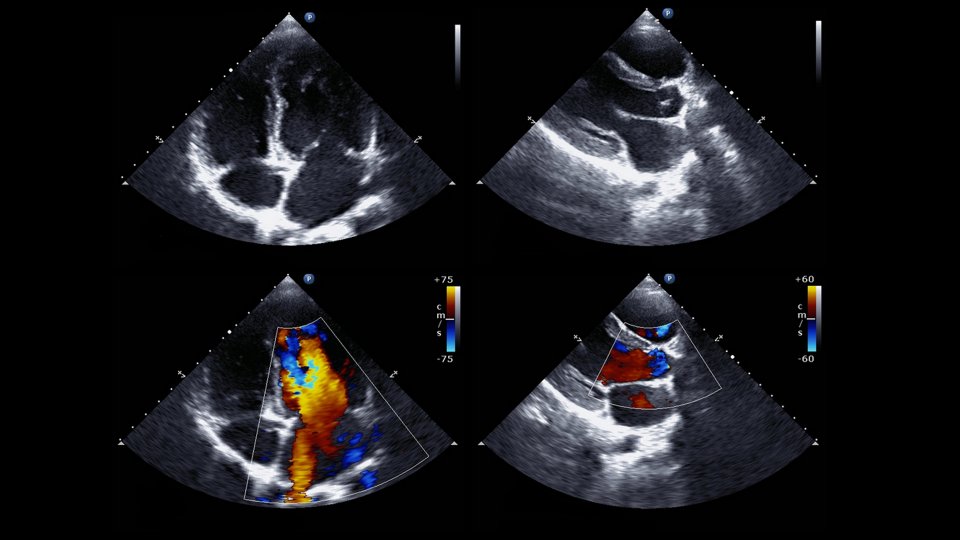

Hastanın göÄŸüs yapısı belirli nedenlerle yeterli kalitede görüntü vermediÄŸinde ya da kalp oluÅŸumlarını daha yakından incelemek gerektiÄŸinde uygulanan bir yöntemdir. TEE olarak da bilinen trans özofageal ekokardiyografi, endoskopik bir incelemedir. Aynı zamanda kalp endoskopisi ve kalp ultrasonu olarak da bilinir.

TEE kalp yapısında pıhtı ya da enfeksiyon araÅŸtırılmasında, aort yırtılmalarının teÅŸhisinde, protez kapak fonksiyonlarının deÄŸerlendirilmesinde, kalp kapağı yetersizliÄŸi durumunun belirlenmesinde, kalp deliklerinin incelenmesinde, kalp kapak ameliyatları ya da kalp delikleri için yapılan cerrahi iÅŸlemlerin sonucunun deÄŸerlendirilmesinde kullanılır.

“TEE nasıl yapılır?” sorusu da merak edilenler arasında. Bu iÅŸlem ucunda ince bir ultrason probu bulunan tüp yemek borusuna yerleÅŸtirilerek uygulanır. Yemek borusu kalbin hemen arkasından geçtiÄŸinde bu inceleme ile kalp ve etrafında bulunan damarlar daha net görüntülenebilir. İşlem uygulanmadan önce hastanın boÄŸazı anestezi spreyi ile uyuÅŸturulur. TEE testi toplamda 30 dakika sürer.